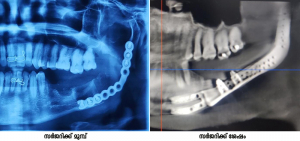

തിരുവനന്തപുരം: സര്‍ക്കാര്‍ മെഡിക്കല്‍ കോളേജുകളില്‍ ആദ്യമായി കീഴ്താടിയെല്ലിന്റെ അതിസങ്കീര്‍ണമായ സന്ധി മാറ്റിവെക്കല്‍ ശസ്ത്രക്രിയ (T.M. Joint Replacement) കോട്ടയം സര്‍ക്കാര്‍ മെഡിക്കല്‍/ ഡെന്റല്‍ കോളേജിലെ ഓറല്‍ & മാക്‌സിലോഫേഷ്യല്‍ സര്‍ജറി വിഭാഗം (OMFS) വിജയകരമായി പൂര്‍ത്തിയാക്കി.